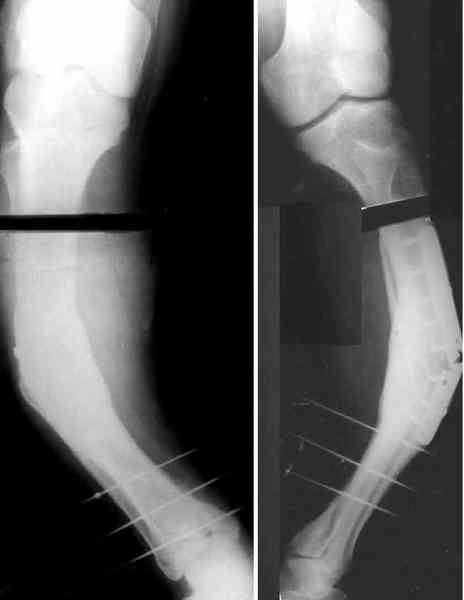

Для продолжения темы - несколько картинок.

Пациент 30 лет, лет пять назад оперирован по поводу перелома голени пластиной. Находясь на героине, нарушил режим, пошел, сломал и ногу и

пластину, но перелом сросся.

В приложении - внешний вид и рентген.

Александр, как раз уровень остеотомии подробнее - на вершине деформации? Там Сломанная пластина.

Там не винты (может, плохо видно), а сломанная пластина, вросшая в кость.

Пластинку и винты мне удалось разглядеть только на профильной проекции, точнее, трехчетвертной, судя по виду коленного сустава (правый снимок). На фасной - вообще не могу разобрать, где она :( Но, в конце концов, можно и не видя ее сказать, что уровень остеотомии может быть и другим, ниже или выше пластинки, придется только компенсировать смещение по ширине, которое появится при полном устранении угла не на вершине.